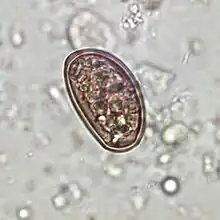

Morphology

Dicrocoelium dendriticum has a similar morphology to Clonorchis sinensis, the Chinese liver fluke. Dicrocoelium dendriticum is distinguished by lobed testes in the anterior of the body, as opposed to Clonorchis sinensis whose testes are located in the posterior. They both are flat and have a characteristic taper at the anterior and posterior ends. The anterior is distinguished by an oral sucker at the point, an acetabulum and the testes. The posterior is where the uterus lies. In the parasite's midsection lie the vitelline glands that are involved in egg formation.

Traditionally, diagnosis for dicrocoeliasis infection involves the identification of Dicrocoelium dendriticum eggs in the faeces of a human or other animal. However, in humans, eggs in the stool may be a result of ingesting raw infected animal liver and may not in fact indicate dicrocoeliasis.[9] Therefore, examining bile or duodenal fluid for eggs is a more accurate diagnostic technique in combination with a liver-free diet.[6]